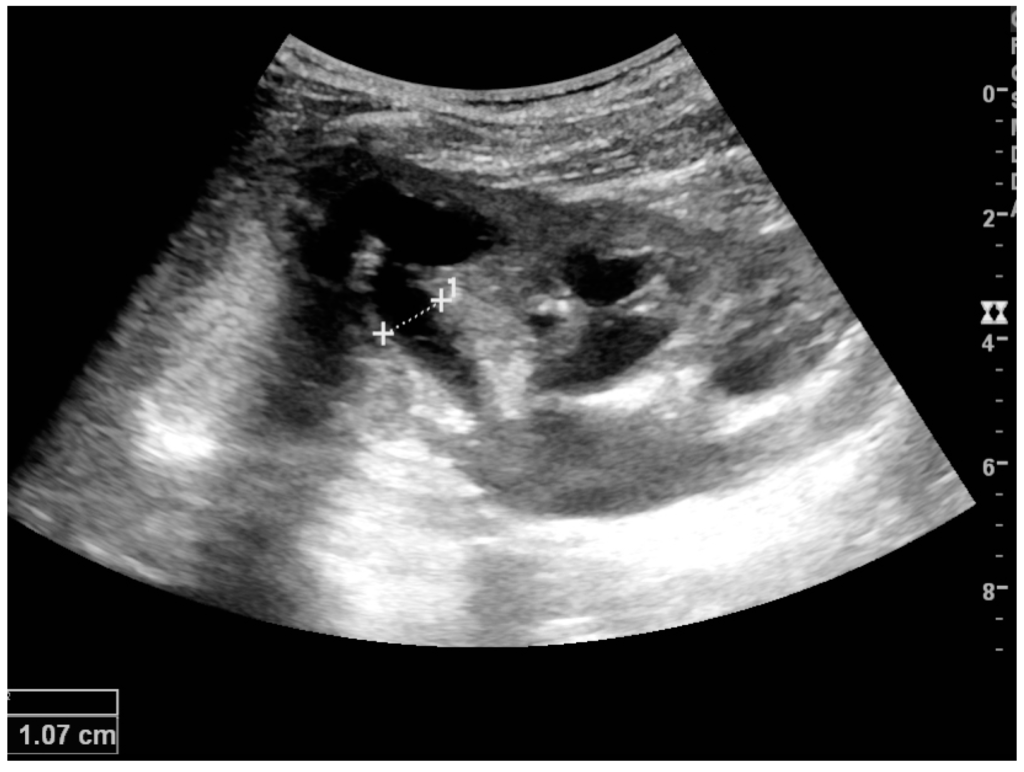

The kidney is divided into parenchyma and renal sinus. The renal sinus is hyperechoic and is composed of calyces, the renal pelvis, fat and the major intrarenal vessels. In the normal kidney, the urinary collecting system in the renal sinus is not visible, but it creates a heteroechoic appearance with the interposed fat and vessels. The parenchyma is more hypoechoic and homogenous and is divided into the outermost cortex and the innermost and slightly less echogenic medullary pyramids [3]. Between the pyramids are the cortical infoldings, called columns of Bertin (Figure 1). In the pediatric patient, it is easier to differentiate the hypoechoic medullar pyramids from the more echogenic peripheral zone of the cortex in the parenchyma rim, as well as the columns of Bertin (Figure 2) [2,4].

Figure 1. Normal adult kidney. Measurement of kidney length on the US image is illustrated by ‘+’ and a dashed line. * Column of Bertin; ** pyramid; *** cortex; **** sinus.